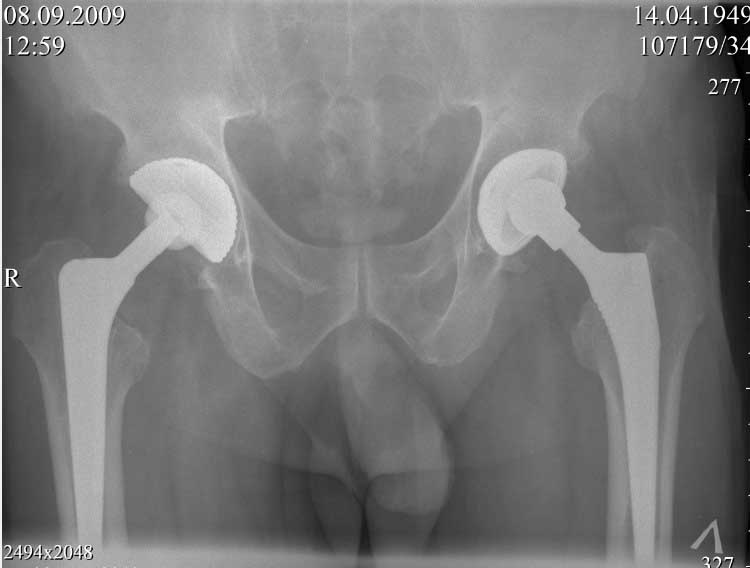

В конце 2008 года отметил боли в правой паховой области при опоре на правую ногу. На рентген снимках таза с тазобедренными суставами явных признаков нестабильности вертлужного компонента не обнаружено. В 2009 году нейрохирурги его "успешно" прооперировали на L\3-\4 связывая болевой синдром в правой паховой области с наличием грыжи указанного межпозвонкового диска. Состояние только ухудшилось, больной уже не мог долго сидеть, боль прогрессировала . Его в 2009 и 2010 годах смотрел ортопед, делались рентгенснимки, но почему то приходили к выводу что эндопротез справа стабилен. В марте 2011 года я впервые увидел его, через одну неделю после этого был прооперирован. На операции вертлужный компонент при упоре на него инструментом прокручивался во впадине и без труда был извлечен.

далее снимок в 2009 году

На заключительных снимках явная нестабильность чашки и вероятная ножки, возможно на повторный прием придет не столь радостный (пессимистический прогноз) надеюсь, что все будет по-другому

Нет вы не поняли! Вы поспешили с выводом! Я не смог выслать окончательный, послеоперационный снимок, по техническим причинам. Я это сделал позже, что Вы и видите ниже! Извините, если я Вас запутал!

С последним, третьим снимком он ко мне и обратился, после чего он был и прооперирован на правом тазобедренном суставе!